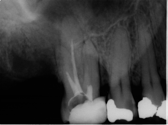

Treatment Examples

Conventional Treatment with Standard Core Restoration

Non-surgical endodontic treatment with resin core build up

Conventional endodontic treatment with alloy core build up

Conventional Endodontic Treatment with Post and Core Coronal Restoration

Conventional Endodontic Treatment/Retreatment with Prefabricated Bonded Post and Core

Conventional Endodontic Treatment with Minimal Clinical Crown: Cast Post and Core Coronal Restoration

Surgical Endodontic Treatment

Hemisection with Cast Post and Core

Surgical Exposure of ECIR with External Cervical Root Repair, Conventional RCT with Prefab Post

MB Root Amputation

Long Term CaOH Cases

12 Month CaOH Treatment

14 Months CaOH Treatment

All Treatment performed by Dr. Brian A. Christopherson